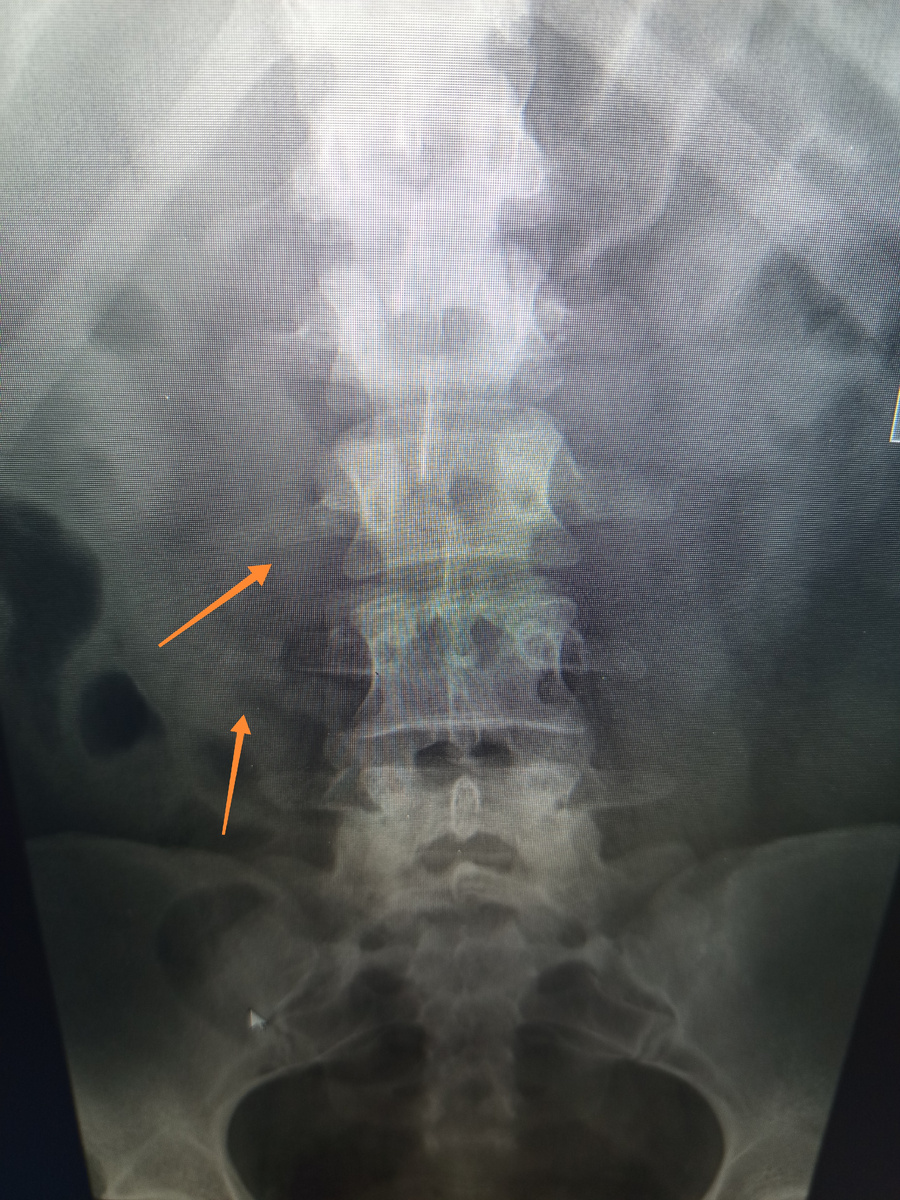

Завезли каталку , женщина , 30 лет. Тоже по сочетке проходит, назначили много исследований , в том числе и поясницу.

Значит , повернем, не надо хамить. Внесла боковую проекцию тоже.

Поперечные отростки отломлены.

Женщина после автодорожки , но только не сегодняшней , а позавчерашней.

Как-то промучилась два дня , но пришлось обратиться.